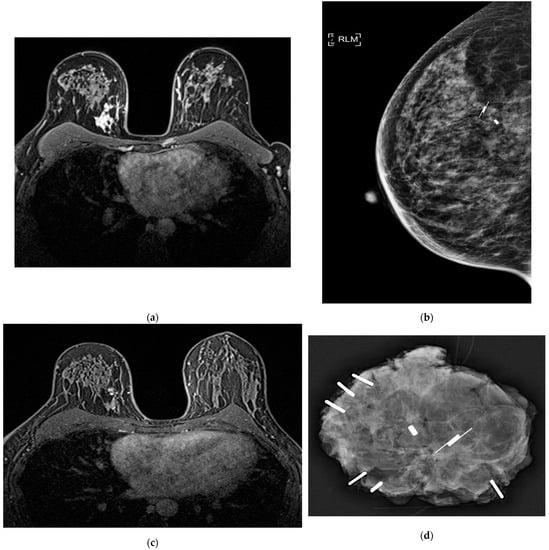

- Goldberg, H.; Zandbank, J.; Kent, V.; Leonov-Polak, M.; Livoff, A.; Chernihovsky, A.; Guindy, M.; Evron, E. Chemotherapy may eradicate ductal carcinoma in situ (DCIS) but not the associated microcalcifications. Eur. J. Surg. Oncol. 2017, 43, 1415–1420. [Google Scholar] [CrossRef] [PubMed]